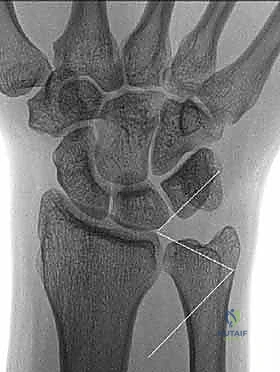

3. كسور الجزء الكردوسي الكردوسي (Ulnar Metaphyseal Fractures)

الجزء الكردوسي هو العنق أو المنطقة الانتقالية التي تربط رأس الزند بجسم العظم (Diaphysis).

هذه المنطقة تحتوي على عظم إسفنجي (Cancellous bone) وهي عرضة للكسور المفتتة (Comminuted fractures) خاصة عند كبار السن المصابين بهشاشة العظام، أو في حالات الحوادث عالية الطاقة. الكسر هنا يؤدي إلى قصر في طول عظم الزند، مما يغير من ميكانيكية توزيع الأحمال في المعصم ويسبب متلازمة انحشار الزند (Ulnar Impaction Syndrome).

توضيح لكسور الجزء الكردوسي الكردوسي